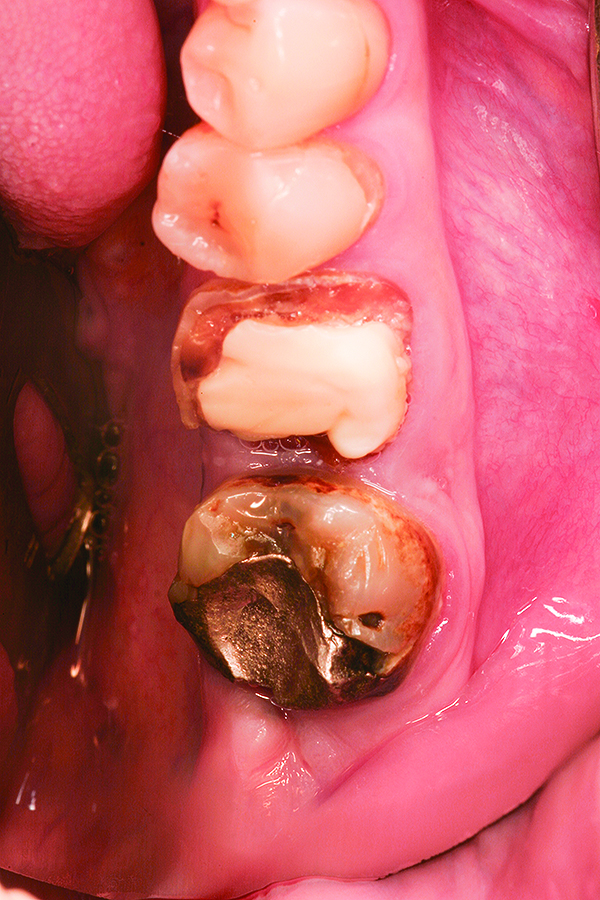

Fig 1. Case 1: Hopeless mandibular first and second molars prior to extraction.

Figure 1

Fig 2. Atraumatic extraction of hopeless mandibular first and second molars.

Figure 2